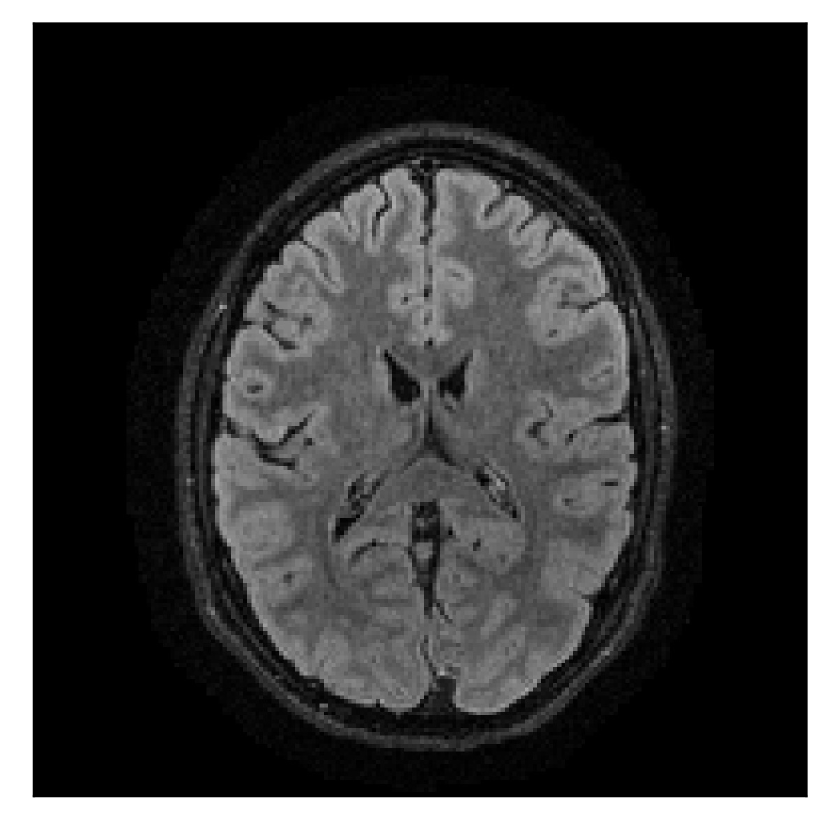

4.1 Experiment 1: robustness test

We gather the results for the robustness test described in Section 3.1 (volunteer 1) in Figures 2, 4, and 6 for motion corruption mechanisms associated to one, two, and five changes of position, respectively. Furthermore, we juxtapose the corrected images with varying degrees of corruption in Figure 8. We observe that the proposed method consistently ameliorates the corrupted scan. The quality indexes based on PSNR and SSIM show only a modest decrease in correction quality as a function of motion complexity (Figure 8).

| Section 3.1, Figure 2 | Sagittal | 23.94 | 27.95 | 0.7068 | 0.7936 |

| Coronal | 26.66 | 29.82 | 0.7653 | 0.8332 | |

| Axial | 25.40 | 30.16 | 0.7616 | 0.8490 | |

| Section 3.1, Figure 2 | T2-FLAIR | Completely corrected | Some blurring | No additional artifacts | Good grey white matter differentiation |